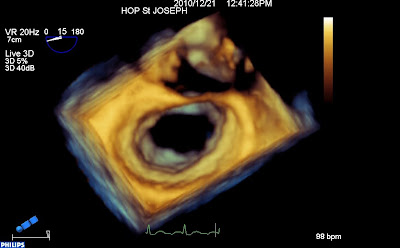

En 3d, (vue « chirurgicale » de l’oreillette gauche habituelle, aorte en haut, auricule à droite) on est d’emblée frappé par la déformation de l’anneau, qui semble aplati sur la commissure antérieure.

Les deux feuillets sont « tractés » vers le ventricule, par le raccourcissement des cordages (le plan de coaptation se situe très en dessous de l’anneau).

La valve ferme au milieu, mais les deux commissures (et surtout l’antérieure) restent ouvertes (et donc fuyantes).

Il s’agit donc d’une fuite rhumatismale, par restriction des deux feuillets, déformation de l’anneau et défaut de coaptation bi-commissurale.

Diastole :

Systole (noter l’absence de coaptation dans les zones commissurales):